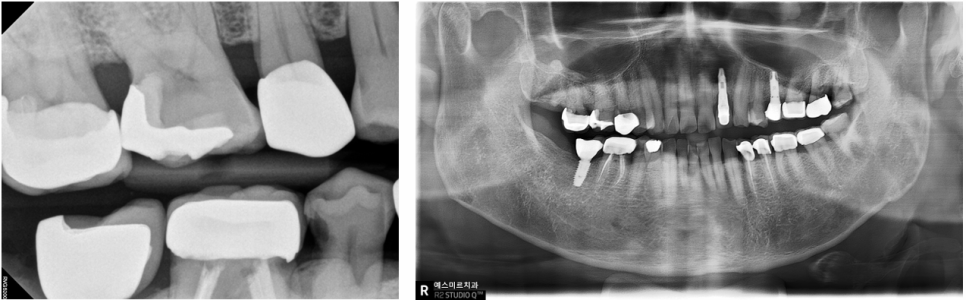

엑스레이 정밀검사

예전 충치 치료 시에도 충치가 꽤 깊었던 흔적이 보입니다

다행히 뿌리 끝에 염증은 보이지 않았어요

기존 inlay를 뜯어서 치아 내부를 확인하고

금이 간 것까지 고려해

치아를 완전히 씌우는 크라운 치료를 하기로 했습니다